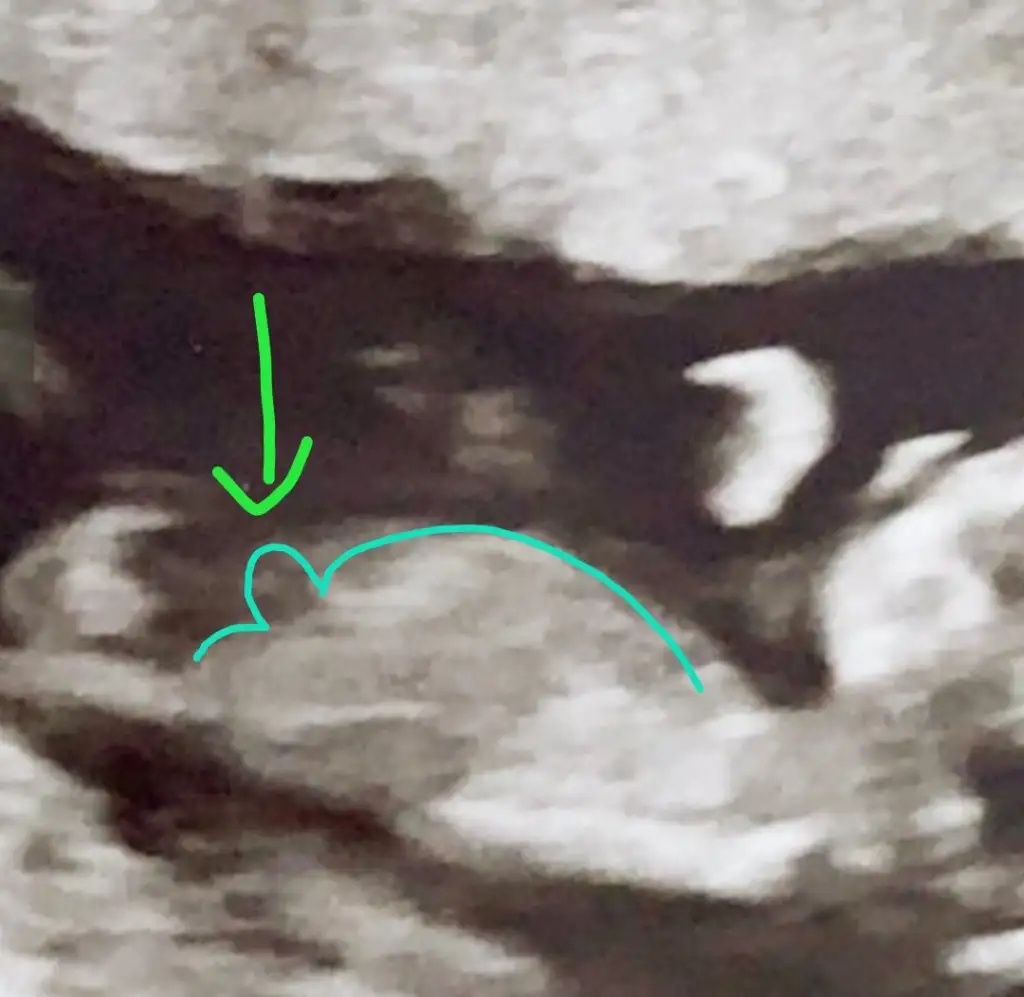

dr soylemeden siz gorun genital nub teorisi ( bebegin cinsiyeti)

Önce kıza benzettim demiştiniz 😊 bilemiyorum ama bunu dik görünüyor gibi ❤️ dikkatlice bakarsanız görürsünüz ❤️